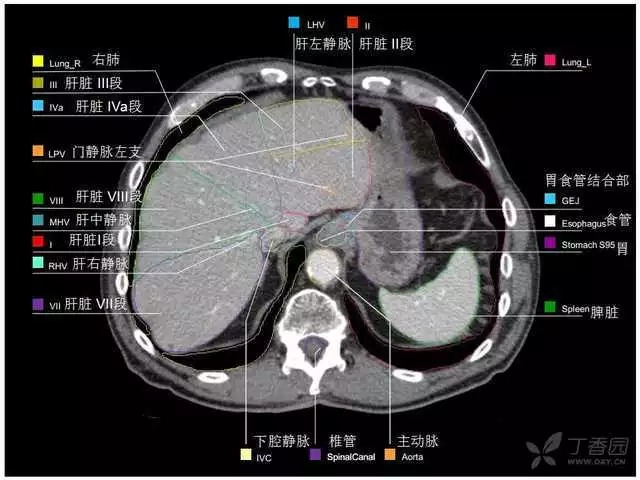

腹部肝脏高清CT断层的图谱

全腹部高清CT图谱,淋巴结彩色图谱,血管解剖图谱大汇总!

超声肝脏分叶及分段

肝脏分段和基本解剖学标志